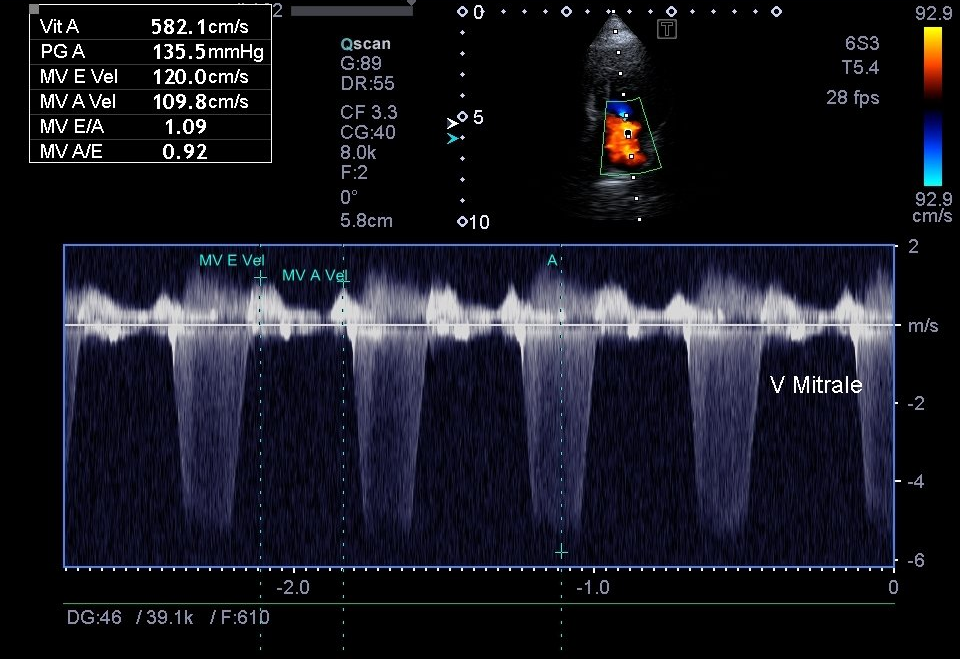

Échographie Cardiaque

L’échocardiographie est utilisée comme son nom l'indique dans l’exploration spécifique du coeur. Elle permet donc particulièrement le suivi des maladies cardiaques.

Nous pouvons mesurer précisément les cavités du coeur, observer la contraction du muscle cardiaque et ainsi visualiser la circulation du sang. Elle peut être complétée par une mesure de la tension artérielle et la réalisation d’un électrocardiogramme, conjointement à d’autres examens comme la radiographie thoracique.